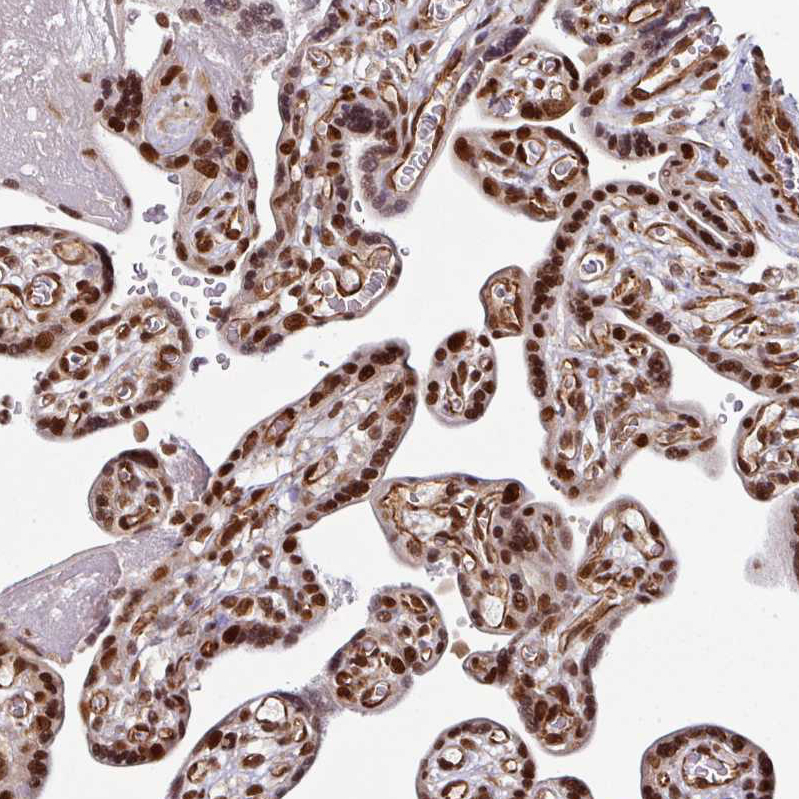

Immunohistochemical staining of human cerebral cortex shows strong nuclear positivity in neurons.